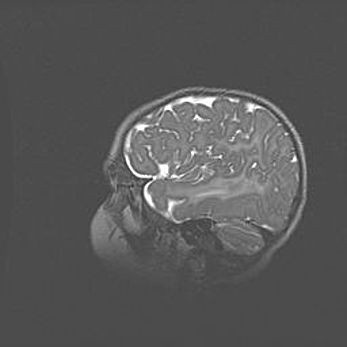

Наружная гидроцефалия с возможной атрофией височных областей.

Возраст: 28 дней

Вес: 3670 г

Пол: мужской

Окружность головы: 38 см

Срок гестации: 40 недель

Гидроцефалия головного мозга у новорожденных – это заболевание, которое характеризуется скоплением избыточного количества спинномозговой жидкости в желудочковой системе головного мозга в результате затруднения её перемещения от места выработки к месту поглощения в кровеносную систему или вследствие нарушения абсорбции. При открытой наружной форме гидроцефалии у новорожденных расширяются и переполняются субарахноидные пространства.

При нормотензивных  формах,  которые,  как  правило,  являются  следствием  перенесенных ишемических  повреждений  паренхимы  мозга,  возможно  сочетание микроцефалии  с нормотензивной гидроцефалией. В основе данных изменений лежит атрофия больших полушарий с преимущественной  локализацией  в  лобно-височных  областях.